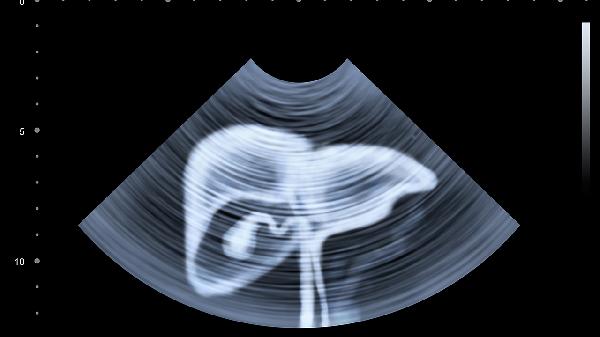

55岁后建议每半年查一次肝功能,每年做次肝脏B超。特别要关注GGT和ALP这两个敏感指标。